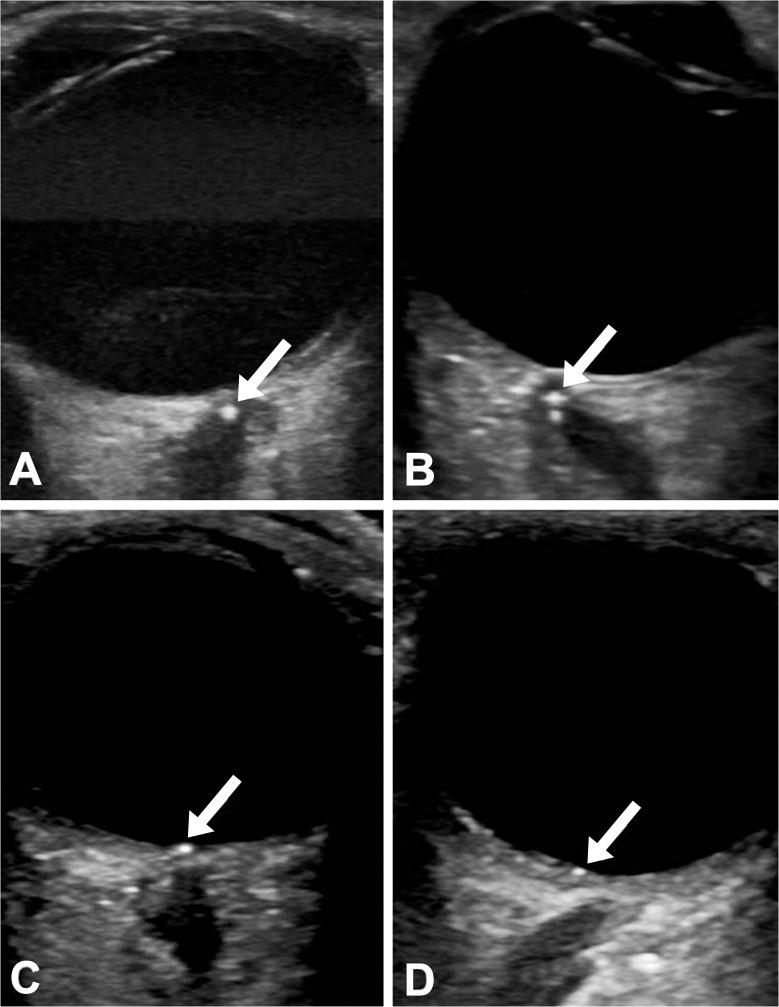

经瞳孔超声检查在老年患者眼部急性动脉阻塞中的应用:“点征”的诊断价值。

Transocular sonography in acute arterial occlusions of the eye in elderly patients: Diagnostic value of the spot sign.

To characterize the diagnostic yield of the spot sign in the diagnostic workup of acute arterial occlusions of the eye in elderly patients.

Clinical characteristics of consecutive patients aged ≥ 50 years with acute central retinal artery occlusion (CRAO), branch retinal artery occlusion (BRAO) or anterior ischemic optic neuropathy (AION) were recorded. Videos of transocular sonography were assessed for the presence of the spot sign by two blinded readers. Group comparisons were made between CRAO-patients with and without the spot sign. Two experienced cardiovascular physicians allocated CRAO-cases to a presumed aetiology, without and with knowledge on the presence/absence of the spot sign.

RESULTS

One-hundred-twenty-three patients were included, 46 of whom suffered from CRAO. A spot sign was seen in 32 of 46 of patients with CRAO and in 7 of 23 patients with BRAO. Interobserver agreement was excellent (Cohen`s kappa 0.98). CRAO-patients with the spot sign significantly more frequently had a medical history of cardiovascular disease (62.8 vs. 21.4%, p = 0.03) and left heart valve pathologies (51.9 vs. 10%, p = 0.03). The spot sign was not found in any of the three patients with CRAO secondary to cranial giant cell arteritis. The assumed CRAO aetiology differed in 37% of cases between two cardiovascular physicians, regardless whether transocular sonography findings were known or not.

CONCLUSION

The spot sign is a simple sonographic finding with excellent interobserver agreement, which proofs the embolic nature of CRAO, but does not allow exact attribution of the underlying aetiology.